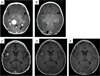

Background: Existing therapies for recurrent or refractory histiocytoses, including Langerhans cell histiocytosis (LCH), juvenile xanthogranuloma (JXG), and Rosai-Dorfman disease (RDD), have limited effectiveness. We report our experience with using clofarabine as therapy in children with recurrent or refractory histiocytic disorders, including LCH (11 patients), systemic JXG (4 patients), and RDD (3 patients).

Results: Patients were treated with a median of three chemotherapeutic regimens prior to clofarabine. Clofarabine was typically administered at 25 mg/m(2) /day for 5 days. Cycles were administered every 28 days for a median of six cycles (range: 2-8 cycles). Seventeen of 18 patients are alive. All surviving patients showed demonstrable improvement after two to four cycles of therapy, with 11 (61%) complete responses, 4 (22%) partial responses, and 2 patients still receiving therapy. Five patients experienced disease recurrence, but three of these subsequently achieved complete remission. All patients with JXG and RDD had complete or partial response at conclusion of therapy. Side effects included neutropenia in all patients. Recurring but sporadic toxicities included prolonged neutropenia, severe vomiting, and bacterial infections.

Conclusion: Clofarabine has activity against LCH, JXG, and RDD in heavily pretreated patients, but prospective multi-center trials are warranted to determine long-term efficacy, optimal dosing, and late toxicity of clofarabine in this population.